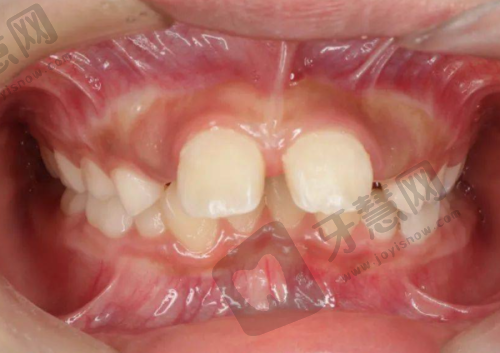

麦芽口腔医院口碑怎样?深圳分院牙齿矫正体验佳

在深圳麦芽口腔做牙齿矫正也是一个不错的选择。有患者前几天在这家店做过洗牙治疗,感觉体验挺不错的。后来来检查牙齿,发现有轻微的牙龈炎,医生给做了牙周刮治,过程中没有任何不适感。患者还带拍了片了解了一下矫正,发现这边的仪器设施都特别精良。医院重视医疗技术,配备新型的诊疗设备和完善的消毒系统,确保患者在一个可靠、卫生的环境中接受治疗。在牙齿矫正方面,通过智能化正畸方案设计软件模拟牙根位移情况,能够精细控制每一步治疗过程,使患者在较短的时间内看到满意的矫正结果。